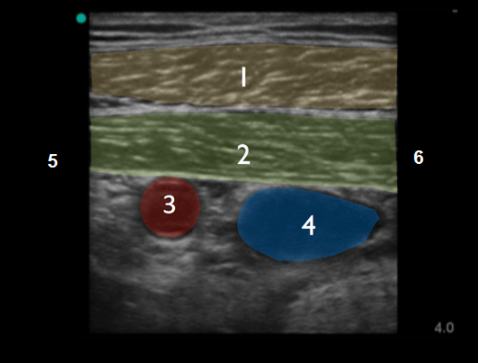

锁骨下超声解剖结构 - 胸大肌和胸小肌图像

胸大肌

胸小肌

腋动脉

腋静脉

头侧

尾侧